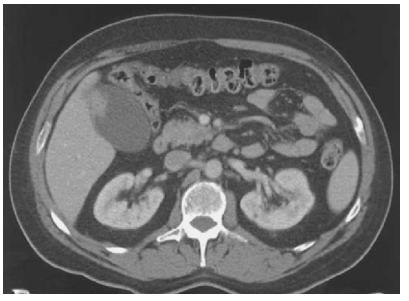

Mulher 57 anos. Assintomática do ponto digestivo. Realizou TC do abdome sem contraste para avaliação de cólica nefrética e suspeita de ureterolitíiase.

Após avaliação da imagem abaixo, você indicaria qual procedimento cirúrgico?

Imagem associada para resolução da questão